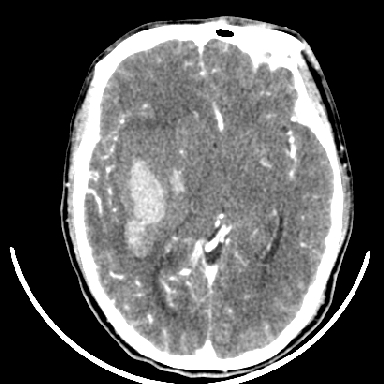

考虑高血压性脑出血,依据:

1是高血压性脑出血的好发部位,形态呈肾形,是高血压性脑出血的常见形状

2增强时占位效应加重了,考虑出血还没有停止

3病灶周围水肿不是太厉害,一般肿瘤出血水肿多非常明显

4病灶周围的‘软组织’影没有明显的强化

5至于脑血管畸形引起的出血,暂时没有看到明显的畸形血管影,也不太支持

支持右侧基底节脑出血

右侧基底节区脑出血.

支持右侧基底节区(主要为外囊区)原发性脑出血。

另附部分资料:“血液溢出血管外形成血肿,其内含有大量血红蛋白、血浆白蛋白,球蛋白,因这些蛋白对x线的吸收系数高于脑质,故ct呈现高密度阴影,ct值达40~90h,最初高密度灶呈非均匀一致性,中心密度更高,新鲜出血灶边缘不清。基底节区血肿多为“肾”型,内侧凹陷,外侧膨隆,因外侧裂阻力较小,故向外凸,其它部位血肿多呈尖圆形或不规则形”